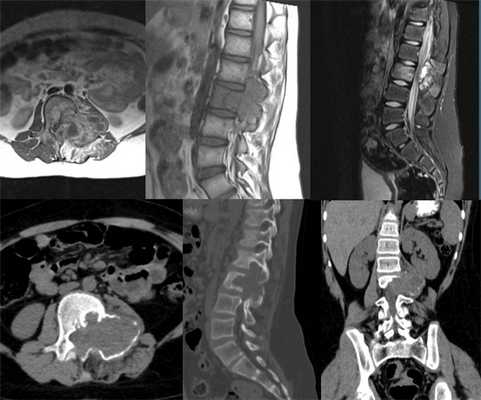

В нашей клинике в стандарт обследования пациентов с подозрением на наличие аневризмальной кисты кости входят рентгенография и компьютерная томография.

Рентгенологически различают два типа аневризмальной кисты - расположенные центрально и эксцентрически. В течение аневризмальных кист выделяют три фазы - остеолиза, отграничения и восстановления.

КТ позволяет выявить характерный для аневризмальной кисты симптом “горизонтальных уровней”, а также относительную плотность для уточнения тактики лечения.

Диагностика заболевания начинается с осмотра ортопедом-травматологом или неврологом. Иногда в ходе него удается пальпировать выпячивание на поверхности кости, а также обнаружить симптомы неврологических нарушений. Но основным методом диагностики является рентген. На полученных снимках можно заметить эксцентрический литический очаг, нередко выходящий за нормальные размеры кости. Дополнительно обнаруживается присутствие характерного склеротического ореола. Сама киста визуализируется в виде многокамерного образования со структурой по типу мыльных пузырей.

Дополнительно для подтверждения диагноза и оценки состояния межпозвонковых дисков, спинного мозга, мягкотканых структур пациентам может назначаться МРТ. Комплекс этих исследований позволяет правильно оценить степень агрессивности костной кисты позвоночника, а также разработать оптимальную тактику лечения.